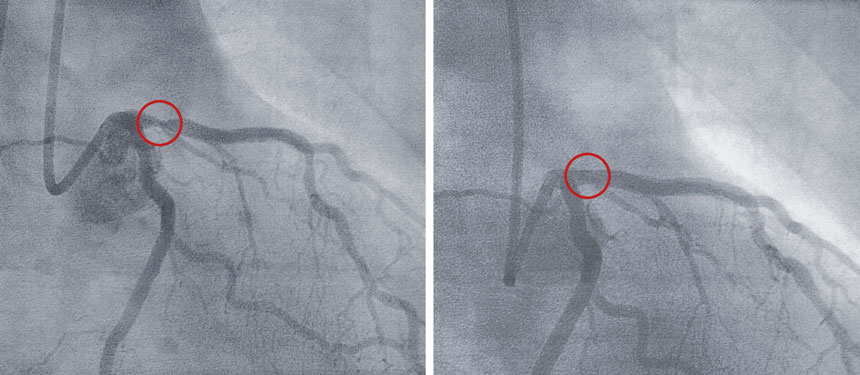

A doctor views an image of the heart during a coronary angioplasty, during which a tube is inserted into the vessels to clear a blocked artery and possibly place a stent. Some patients with heart disease could avoid this procedure and treat their condition with medical therapy alone, researchers say.

The federally-funded study, called ISCHEMIA, is the largest clinical trial to examine whether medical therapy alone, or along with stents or bypass surgery, reduces death or heart attacks in patients who have heart disease primarily due to plaque-containing, narrowed coronary arteries, but who have manageable pain or other symptoms. The participants in the invasive procedure group had a device threaded through the arteries, followed by placement of a stent to keep an artery open or else bypass surgery to divert blood flow around a blockage. The procedures come with risks such as bleeding or the formation of blood clots that can block an artery again.